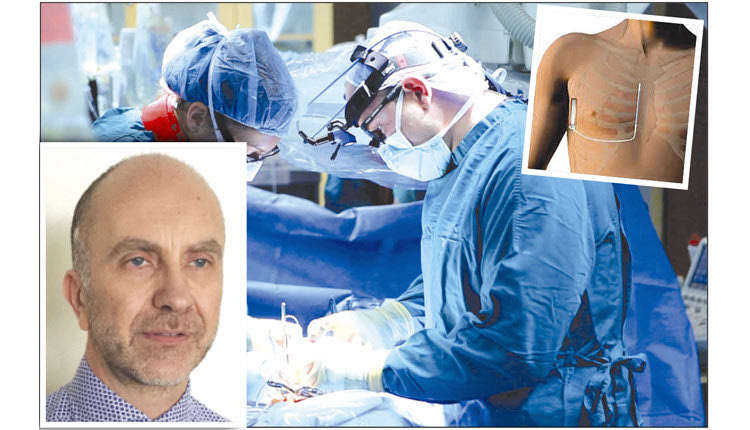

Σε μια ακόμη καινοτόμα επέμβαση, που γίνεται για πρώτη φορά στην Κρήτη και πραγματοποιείται σε λίγα εξειδικευμένα κέντρα στην Ελλάδα και το εξωτερικό, προχώρησαν οι γιατροί της Καρδιολογικής Κλινικής του Πανεπιστημιακού Νοσοκομείου Ηρακλείου.

Σε ασθενή με καρδιακή ανεπάρκεια που κινδύνευε από αιφνίδιο θάνατο εμφυτεύθηκε υποδόριος απινιδωτής αφήνοντας ανέγγιχτα την καρδιά και τα αγγεία.

Η επέμβαση πραγματοποιήθηκε στο Εργαστήριο Αρρυθμιών, Ηλεκτροφυσιολογίας και Βηματοδότησης της Καρδιολογικής Κλινικής του ΠΑΓΝΗ από τον διευθυντή Ε.Σ.Υ κ. Μ. Κανουπάκη, με τη συνδρομή του θωρακοχειρουργού κ. Ι. Δροσίτη και την συνεργασία του αναισθησιολογικού τμήματος του νοσοκομείου.

“Η Καρδιολογική Κλινική του ΠαΓΝΗ συνεχίζοντας να πρωτοπορεί στην καινοτομία και στις νέες εξελίξεις στην Καρδιολογία τόσο σε διαγνωστικό, όσο και σε θεραπευτικό επίπεδο πραγματοποίησε σήμερα (σ.σ. χθες), την πρώτη εμφύτευση εξ ολοκλήρου υποδόριου απινιδωτή σε ασθενή 63 ετών με διατατική μυοκαρδιοπάθεια, αυξημένου κινδύνου, για αιφνίδιο καρδιακό θάνατο” είπε στην “Π” ο διευθυντής της Καρδιολογικής Κλινικής καθηγητής Φραγκίσκος Παρθενάκης, τονίζοντας ότι είναι σημαντική η στήριξη της διοίκησης στις πρωτοπόρες αυτές επεμβάσεις.

Ο υποδόριος απινιδωτής αποτελεί εξέλιξη των τελευταίων ετών και έχει σκοπό να αφήσει τα αγγεία και την καρδιά εντελώς ανέγγιχτα αφού τοποθετείται εξ ολοκλήρου κάτω από το δέρμα, μειώνοντας στο ελάχιστο, τις πιθανές επιπλοκές της αγγειακής προσπέλασης και της ενδοκαρδιακής τοποθέτησης των ηλεκτροδίων των συμβατικών απινιδωτών.Να σημειωθεί οτι στο Εργαστήριο πραγματοποιούνται σήμερα όλες οι τεχνικές της σύγχρονης Επεμβατικής Αρρυθμιολογίας από την ομάδα η οποία απαρτίζεται από τον καθηγ. κ. Ε. Σημαντηράκη και τους ιατρούς Ε.Σ.Υ κ. Ε. Καλλέργη και κ. Η. Μαυράκη.

“Η επέμβαση που έγινε, τόνισε ο κ. Παρθενάκης, “ανοίγει ένα νέο πεδίο και επιβεβαιώνει τις υψηλού επιπέδου υπηρεσίες υγείας που παρέχει η Καρδιολογική Κλινική στον πληθυσμό της Κρήτης”.